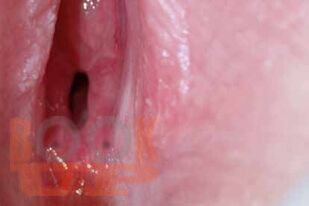

Судебно-медицинская экспертиза акушерско-гинекологическая и половых состояний мужчин : учебно-методическое пособие / Е. Х. Баринов, А. В. Максимов, М. А. Кислов и др. - М. : Практическая медицина, 2025. - 132 c.. - (Библиотека судебно-медицинского эксперта). - ISBN 9785988118312. - Текст : электронный // ЭБС "Букап" : [сайт]. - URL : https://www.books-up.ru/ru/book/sudebno-medicinskaya-ekspertiza-akushersko-ginekologicheskaya-i-polovyh-sostoyanij-muzhchin-19593859/ (дата обращения: 11.05.2026). - Режим доступа : по подписке.